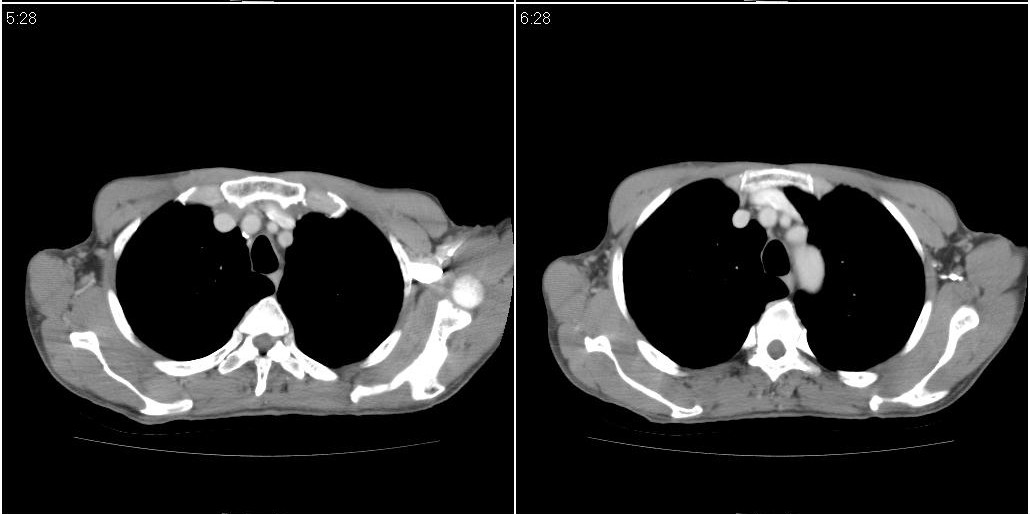

以下是ct检查的情况:

标题: ct增强:

右肺中叶阻塞性不张及肺炎,高度怀疑支气管占位,建议纤支镜检查!

1)右肺中叶慢性炎症并支气管扩张,节段性肺不张。2)两肺下叶支气管扩张。